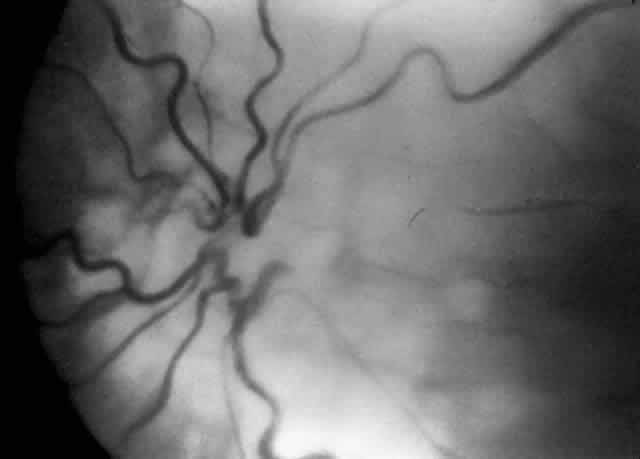

When first assessing a child's retinal detachment, one must judge the amount of effusive versus tractional detachment (Figs. 4 and 5). Scleral buckling would be considered for the child who shows a predominately effusive stage 4B detachment as opposed to a stage 4 predominately tractional detachment, for which lens-sparing vitrectomy may be recommended.24 For a child who has a great deal of retrolenticular touch, lensectomy/ vitrectomy and membrane peeling would be recommended. It appears that the “window” for lens-sparing vitrectomy may be rather brief. In one series, the postconceptual age of the lens-sparing vitrectomized eyes was 42.6 weeks, as opposed to 46.9 weeks for eyes that needed lensectomy/vitrectomy and membrane peeling. This small time difference in the postconceptual age shows the often rapid evolution of this detachment from one in which the lens is salvageable to one in which the lens is unsalvageable. This highlights the need for timely screening of eyes, identification of eyes with progressive disease, and rapid intervention.25

A child's retinal detachments progress at variable rates; thus the rate of detachment must be assessed on an individual basis. In children with RUSH disease, the eye has a very immature retina with much of the vascularized/avascular retinal juncture in zone 1. These eyes tend to progress to retinal detachment very quickly, often within 1 to 2 weeks. We have described another uncommon entity called very posterior zone 1 retinopathy of prematurity.29 In this disease, the macula is disorganized and not clearly visible. The posterior pole presents a syncytium of vessels all in zone 1. All of these eyes that we followed have gone on to have tractional retinal detachment. If there is to be any hope of vision in these patients, management requires a very rapid and broad peripheral ablative treatment followed by early vitreous surgery intervention.